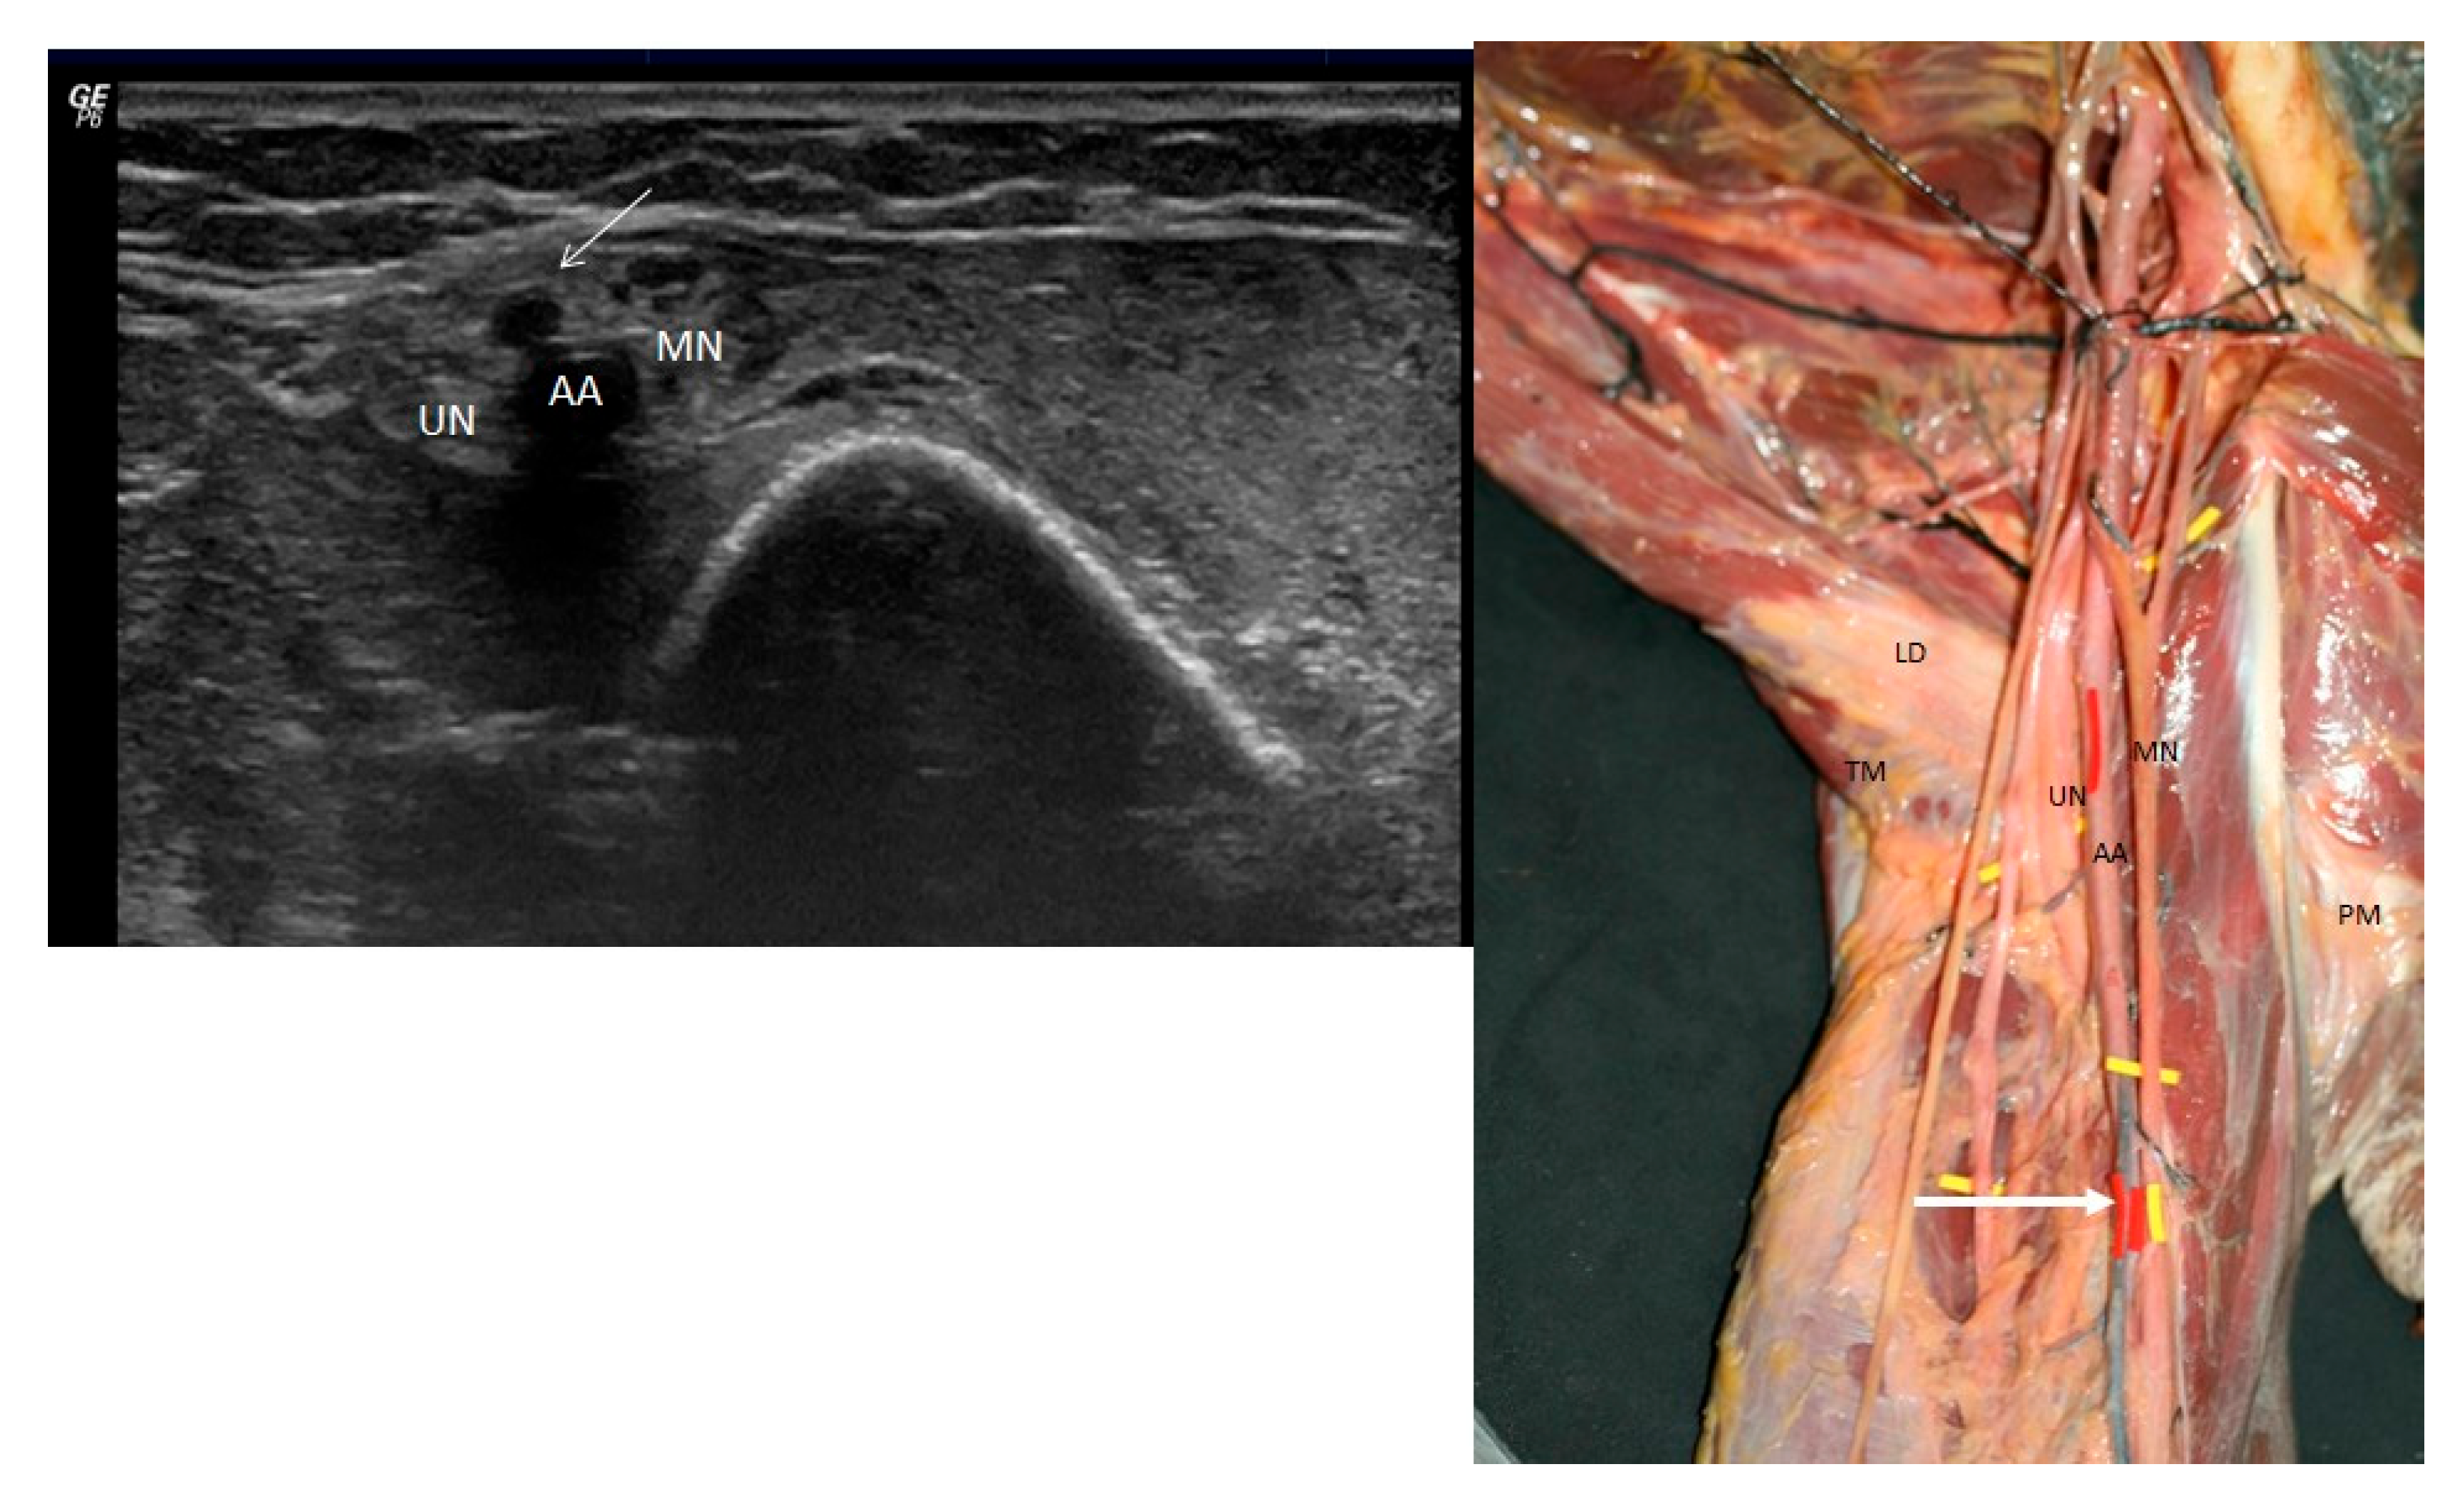

3.1. Ultrasound Study

3.2. Anatomical Study